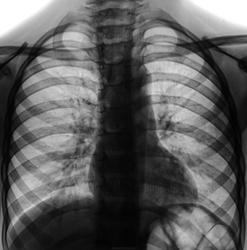

Более выраженное расширение корня правого легкого, нечеткость медиальных отделов правой половины купола диафрагмы, не исключают наличие пневмонии в нижней доле правого легкого.

Прикорневой рисунок справа усилен, явной инфильтрации не вижу.

Пневмонии тоже не вижу. Русунок усилен с обеих сторон по типу острого бронхита, в основном, за счёт сосудистого компонента.

Пневмонии тоже не вижу. Рисунок усилен с обеих сторон по типу острого бронхита, в основном, за счёт сосудистого компонента.

Пневмонии тоже не вижу. Что касается рентгенодиагностики бронхита - считаю, что это должно решаться клинически, а вот выраженные явления обструкции отмечаю. Усиление легочного рисунка у детей, имхо, крайне неспецифично и встречается при любой интоксикации. Часто вижу его, например, у детей с клиникой острых абдоминальных болей, которых присылают для исключения пневмонии.